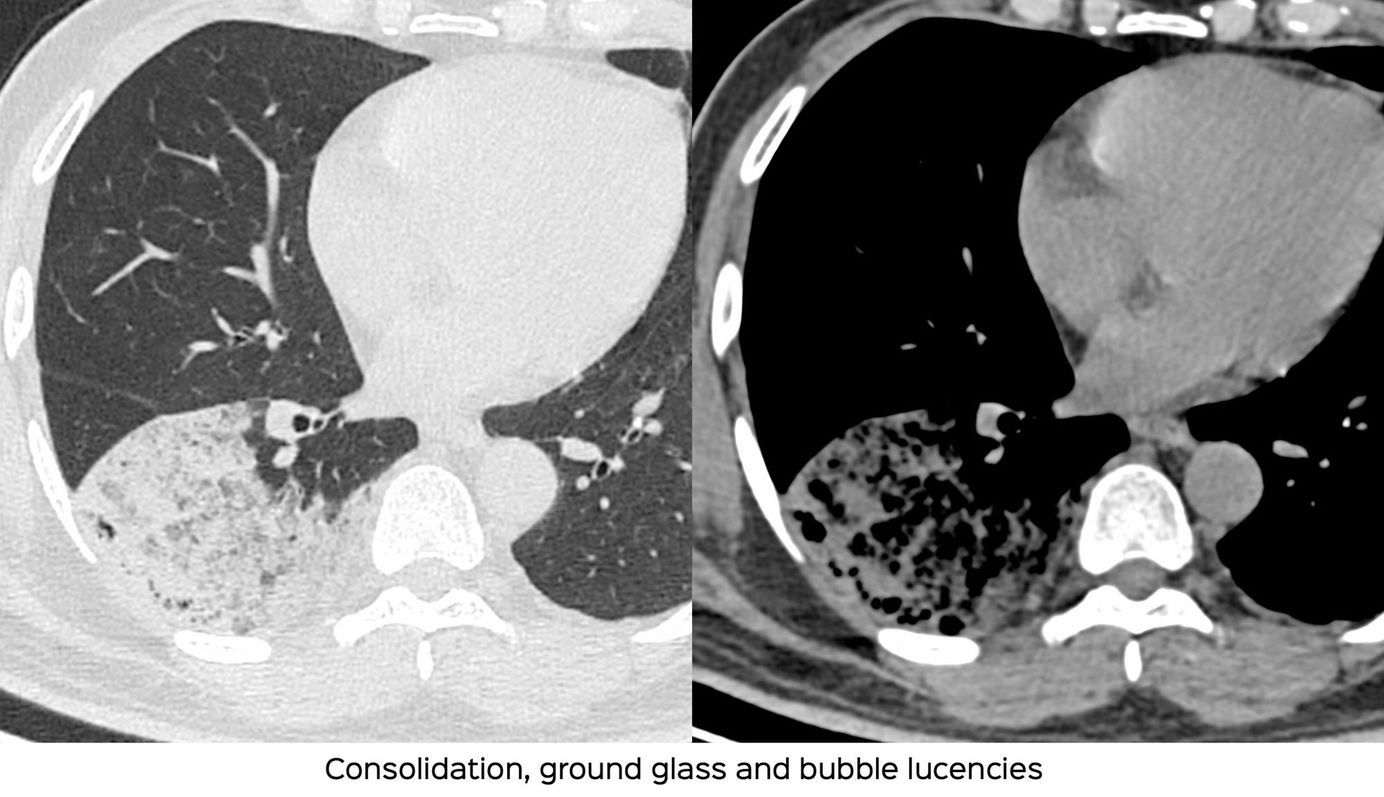

Case 9: Non-Resolving Consolidation and Multifocal Opacities Members Public

64-years old with a non-resolving consolidation and multifocal opacities who finally had a confirmed diagnosis of invasive mucinous adenocarcinoma.

Bhavin Jankharia

Non-Resolving Consolidation